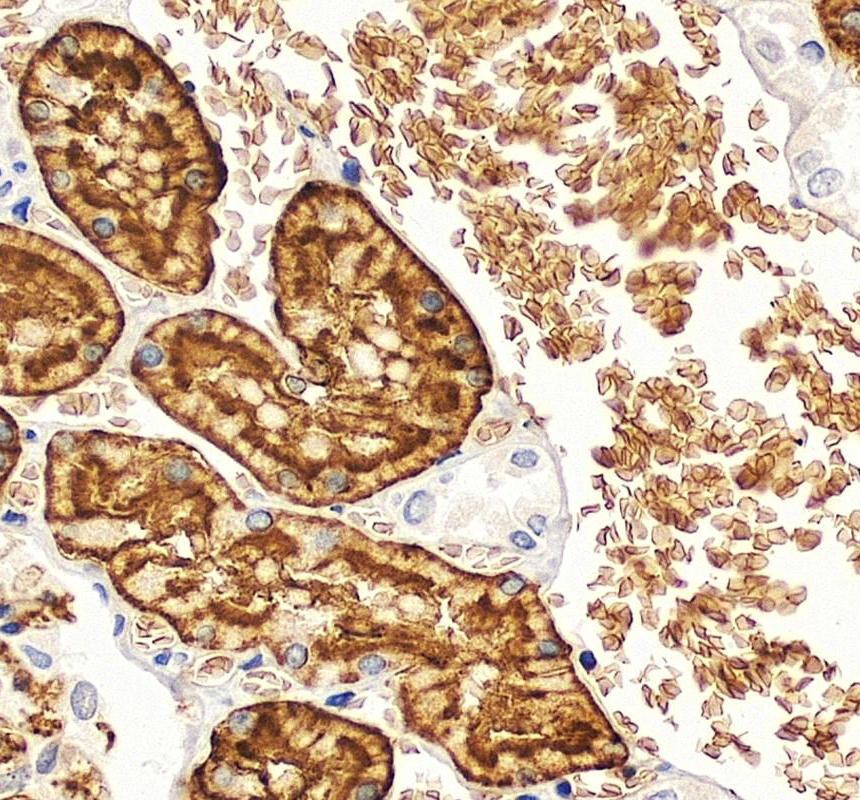

IHC analysis of AQP1 using anti-AQP1 antibody (PB9473).

AQP1 was detected in a paraffin-embedded section of human kidney tissue. The tissue section was incubated with rabbit anti-AQP1 Antibody (PB9473) at a dilution of 1:200 and developed using HRP Conjugated Rabbit IgG Super Vision Assay Kit (Catalog # SV0002) with DAB (Catalog # AR1027) as the chromogen.